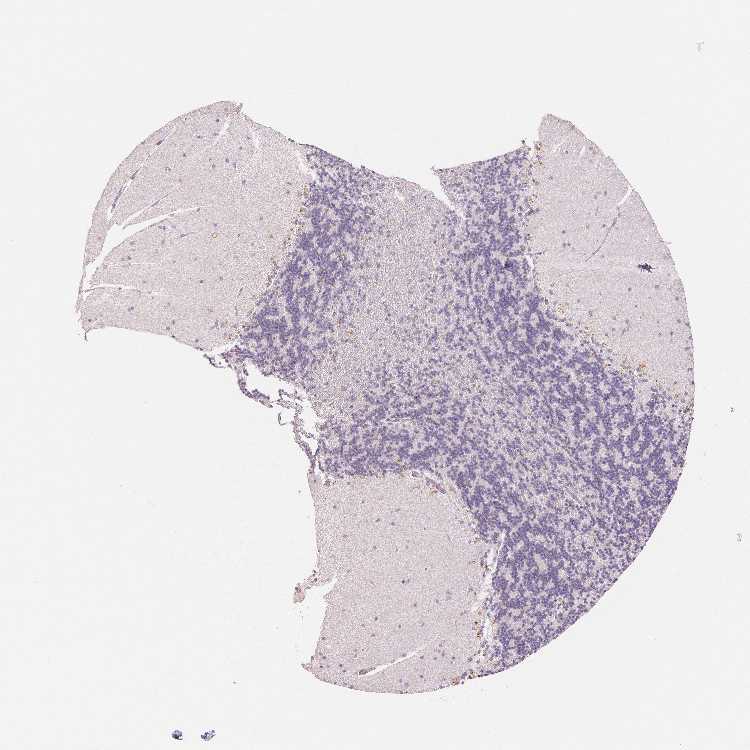

CEREBELLUM - Antibody stainingi

Antibody staining in the annotated cell types in the current human tissue is reported as not detected, low, medium, or high, based on conventional immunohistochemistry profiling in selected tissues. This score is based on the combination of the staining intensity and fraction of stained cells.

Each image is clickable and will lead to virtual microscopy that enables deeper exploration of all samples and also displays staining intensity scores, fraction scores and subcellular localization as well as patient and tissue information for each sample.

Antibody HPA051778Antibody HPA058590Antibody CAB001721

Purkinje cells Not detectedNot detectedNot detected

Cells in granular layer Not detectedMediumNot detected

Cells in molecular layer Not detectedNot detectedNot detected